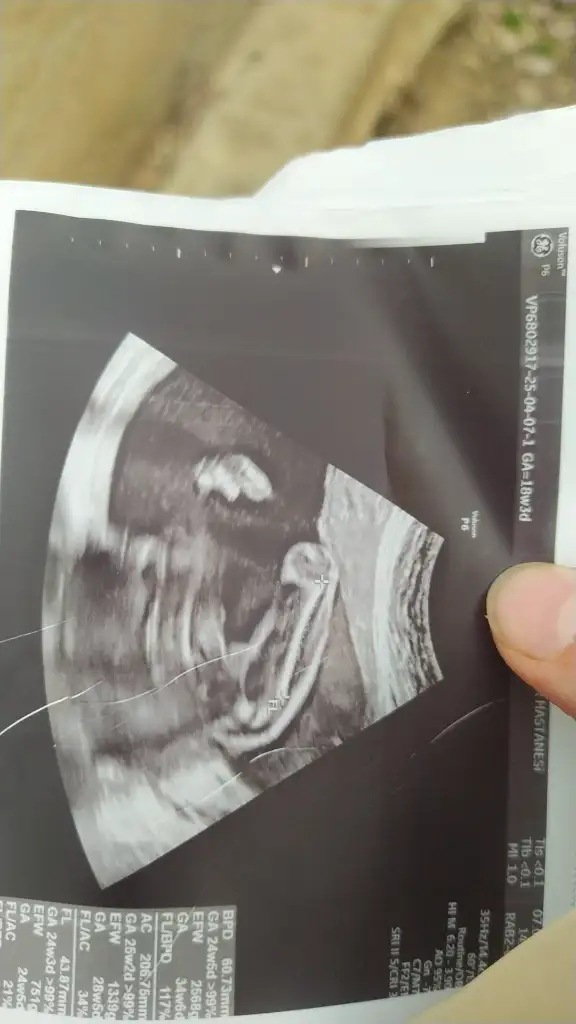

Kızlar sizce nuba göre cinsiyet nedir 12+5

Eklentiler

• IMG_2188.webp

24 KB · Görüntüleme: 726